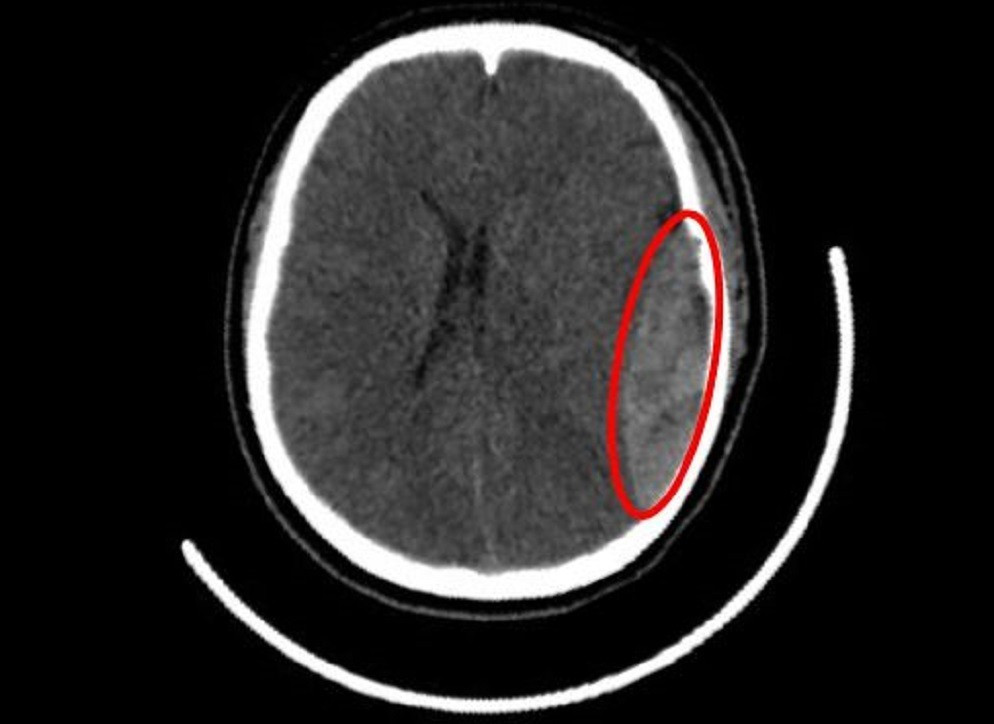

Tại đây, các bác sĩ nhanh chóng thăm khám và ghi nhận người bệnh yếu nửa người bên phải, điểm tri giác theo thang Glasgow là 9-10/15. Chụp MSCT sọ não cho thấy một khối máu tụ ngoài màng cứng ở bán cầu não trái lan xuống cực thái dương trái, kèm theo nứt xương sọ vùng thái dương trái.

Tình trạng hiện tại có xu hướng chảy máu thêm, đánh giá ban đầu cho thấy nguồn chảy máu xuất phát từ nứt sọ thái dương và đứt động mạch màng não giữa. Trước tình hình này, nữ sinh được chỉ định phẫu thuật cấp cứu để lấy máu tụ ngoài màng cứng và cầm máu.

Hình ảnh kiểm tra ghi nhận vị trí nứt hộp sọ, máu tụ dưới màng cứng nữ sinh gặp phải/Ảnh tienphong.vn